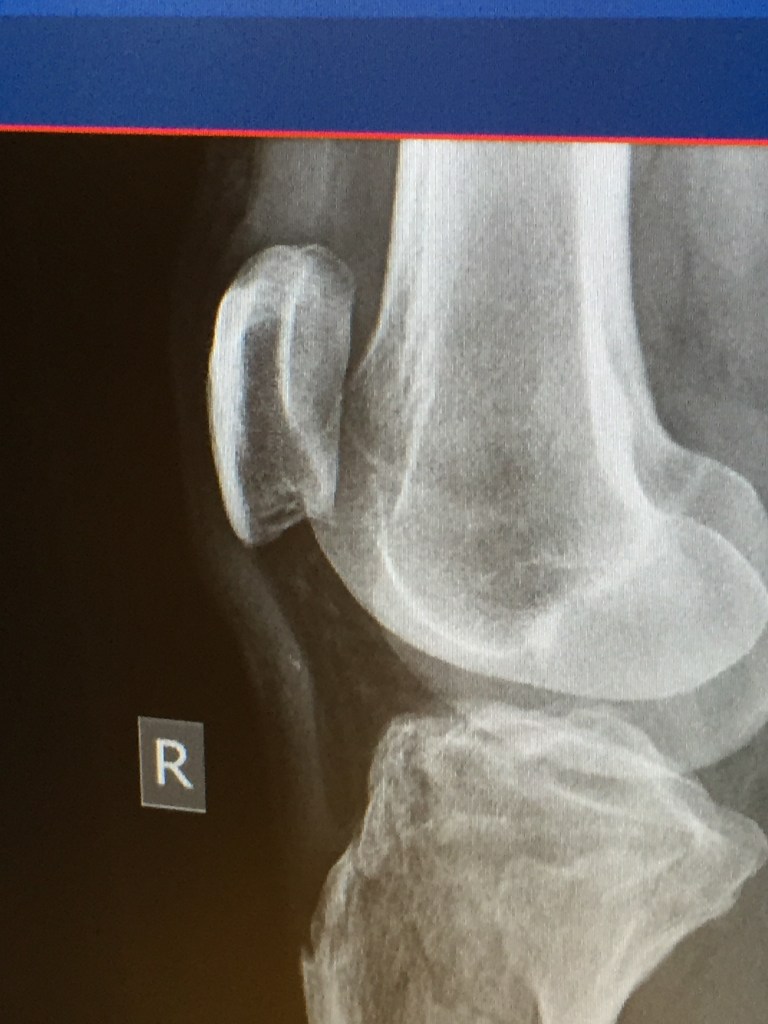

Made return trip to FL – no vehicle issues this time. While taking the Cannon off the trainer and placing the rear wheel back on, discovered a broken spoke on the Hed wheel. Wouldn’t be using the primary randonneuring bike, 2017 Cannondale SuperSix Evo (Cannon), for the weekend rides. Didn’t have any other rim brake wheels in FL. Will have to fix that shosrtcoming depending upon how long it remains the randonneuring bike. Remounted the front light and handlebar bag back on Wili and loaded it in the car. Forgot to take the rear light off the Cannon but thankfully had my secondary light on the back of my helmet. Would only need the lights for a little over an hour as the 300K started at 0600 and the 200K at 0700. Saturday was cold and windy. Rode with Recumbent Man and 2 others for the entire day. Temps were in the high 30s but had a 15+ mph wind which pushed us to a 20.8 mph average for the first 95 miles. The return took about an hour longer and the 3 of us took turns behind Recumbent Man as he pulled us back. Legs definitely lost endurance over the last half of December and first week of January. Sunday was a colder start for the 200K but didn’t feel as cold as the wind was much more mild. Had navigational challenges early on – within first 3 miles, Garmin route indicated a U-turn. Realized the error but had to climb the steep hill twice (rear cassette is only 11-25) and put me at the rear of the group. Ended up catching everyone but Recumbent Man was just departing the turnaround spot as I rolled in. Entire ride for both him and me were solo efforts. Garmin Edge died at the last rest stop with 21 miles to go. Had to use RideWithGPS but for whatever reason, didn’t have any turn-by-navigations so had to have the phone in hand or frequently place/remove it from the handlebar bag. Not a very enjoyable last 20 miles. Front derailleur needs adjustment as the rub in certain gears was very irritating. Successfully completed the ride and enjoyed the post ride pizza! Received bad news 15 minutes before start of 200K – Dad fell and fractured his right hip, shoulder, and 3 ribs along with a collapsed lung.

The only photos are a new pasta casserole (southwestern chicken pasta bake) and the x-ray depicting my father’s new internal hardware.